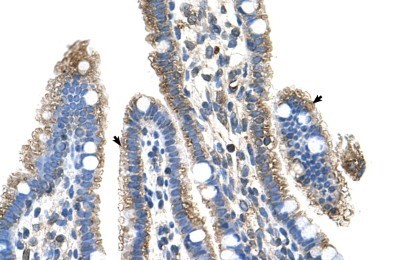

Supportive validation

- Submitted by

- Novus Biologicals (provider)

- Main image

- Experimental details

- Immunohistochemistry-Paraffin: SLC25A39 Antibody [NBP1-59600] - Human Intestine Tissue, antibody concentration 4-8ug/ml. Cells with positive label: Epithelial cells of intestinal villus (indicated with arrows) 400X magnification.